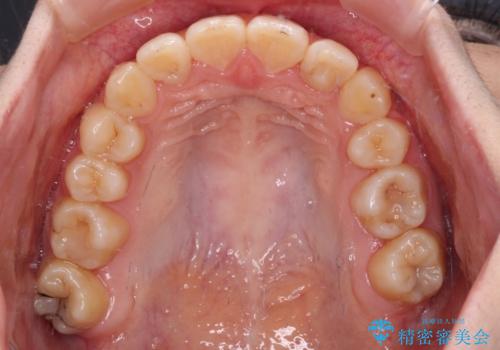

まずは補助装置を用いて八重歯を改善し、インビザラインにて歯列を整えましたが、当初の懸念が的中し、臼歯部の咬合を安定させることができませんでした。

海外留学の予定もあったため、後半は上下ワイヤー装置にて矯正治療を継続し、違和感なく咬合させることとなりました。